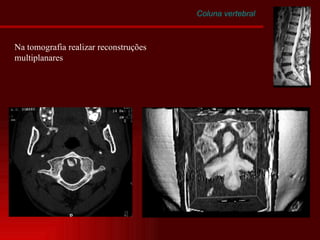

Coluna vertebral Na tomografia realizar reconstruções multiplanares